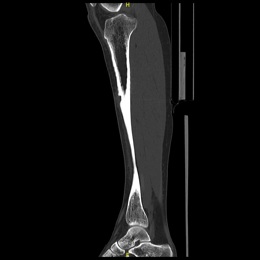

The empty bone cavity is usually filled with bone graft or bone cement. Bone can be donated (allograft) or taken from the patient themselves (autograft). Fixation devices, such as a plate and screws, may be used in specific situations to prevent postoperative fracture. This example of an X-ray shows the bone graft filled in nicely. It looks particulate. In this case, the patient was placed in a cast to protect from fracture and allow the graft to heal.